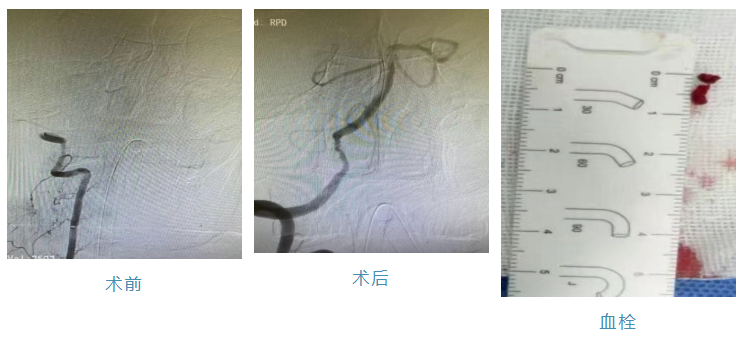

病历3:患者67岁男性,因“头晕、走路不稳2小时”入院,完善颅脑CT未见出血,急诊值班医师与患者家属沟通病情后给予静脉溶栓治疗,同时完善颅脑MR+MRA检查,MRA提示椎基底动脉未见明显显影,邀请神经内三科会诊,张松副主任查看患者后结合患者今年5月份在我院的MRA检查,考虑为大血管闭塞,症状有继续加重的可能,与患者家属充分沟通病情后行急诊脑血管造影检查显示双侧椎动脉V4段闭塞,行急诊取栓术,术后患者完全恢复正常。